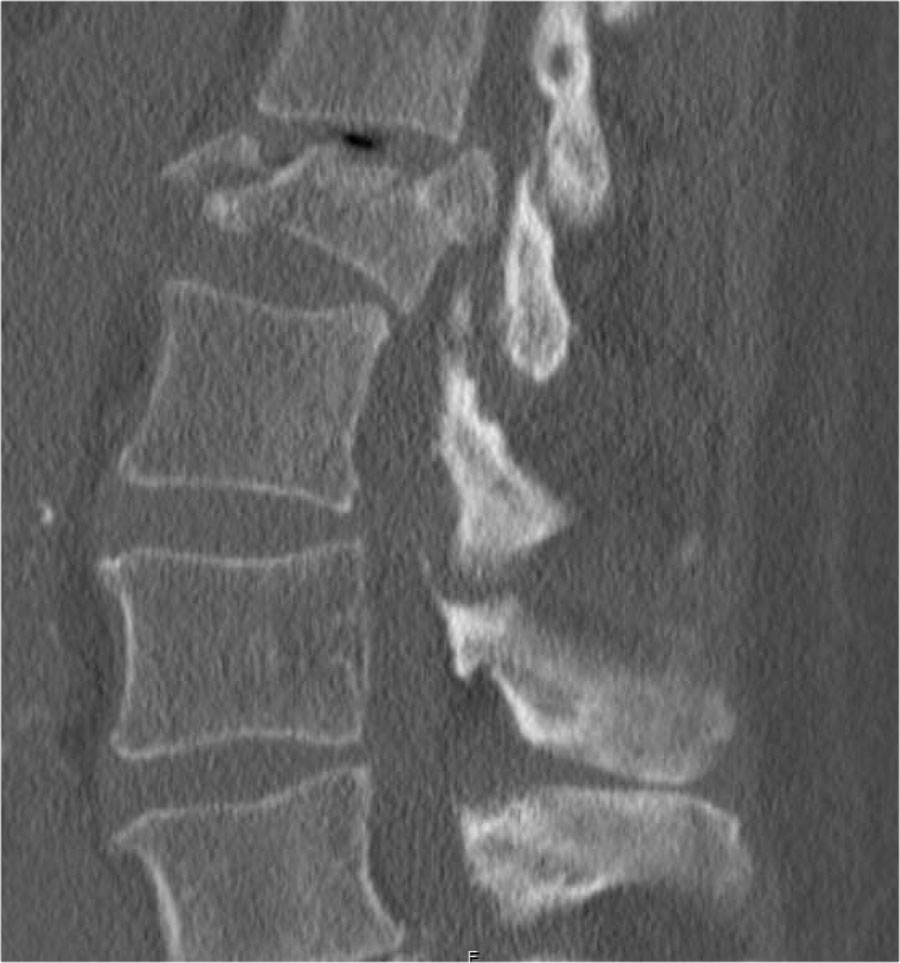

Mảnh xương góc sau trên thân đốt sống bị đẩy lùi ra sau (Retropulsion)

Hiện tượng mảnh xương bị đẩy lùi ra sau là đặc điểm điển hình của gãy vỡ, phân biệt rõ ràng với gãy nén đơn thuần.

Cuộn qua các hình ảnh.

Gãy theo mặt phẳng đứng dọc của thân đốt sống và

cung sau đốt sống

Gãy theo mặt phẳng đứng dọc của thân đốt sống và gãy cung sau theo mặt phẳng đứng dọc gặp lần lượt trong 90% và 85% các trường hợp gãy vỡ.

Dưới đây là bốn ví dụ minh họa.

Trong phân loại Denis, đây sẽ là gãy ba cột — trước/giữa/sau — cho thấy gãy xương rất không vững.

Tuy nhiên, trong phân loại TLICS, đây là gãy vỡ, tức là 2 điểm cho hình thái.

Phương pháp điều trị sẽ phụ thuộc vào tính toàn vẹn của PLC và tình trạng thần kinh.